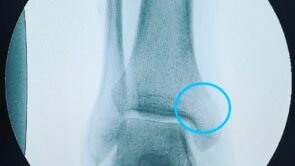

Реконструкция медиальной лодыжки свободным аутотрансплантатом из гребня подвздошной кости после травматического дефекта: клинический случай

Введение Открытые переломы медиальной лодыжки, сопровождающиеся невозможностью ее остеосинтеза вследствие утери костного фрагмента либо его массивной фрагментации, довольно редки в клинической практике. Медиальная лодыжка необходима для обеспечения стабильности голеностопного сустава, и ее реконструкция важна для возможности восстановления функциональных результатов. В мировой литературе описано несколько методик реконструкции, которые можно разделить на две группы: 1) реконструкция свободными...